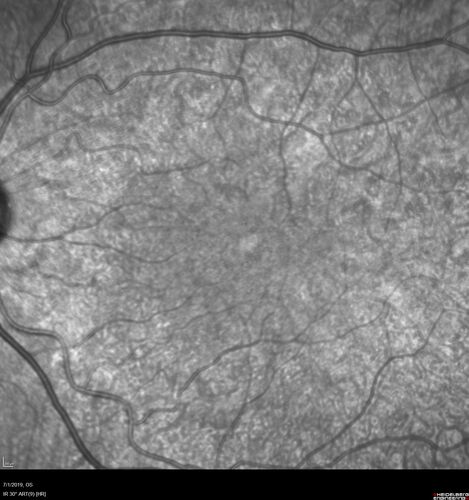

Ocular Lymphoma - Initially presented like auto-immune retinopathy

43 year old man: initial presentation - The vision in the left eye is blurry and opaque for about 2 weeks.  In the central of the vision, when he covers the right eye, in the center of the left eye there is a film with a light in the middle.  This has never happened before.  He has not been sick for the last few months.  A few weeks ago he saw waves on the floor when looking down but that has gone away.  Since the vision loss started the vision has not changed much.  The central vision is not getting better.

Labs normal.  One positive antiretinal antibody - Arrestin

VA improved over 2 months to normal.  Then the patient had 2 more episodes of self-limited vision loss (no treatment).  Then 2 years later he presented with a diagnosis of CNS lymphoma and later developed subretinal deposits (last images)